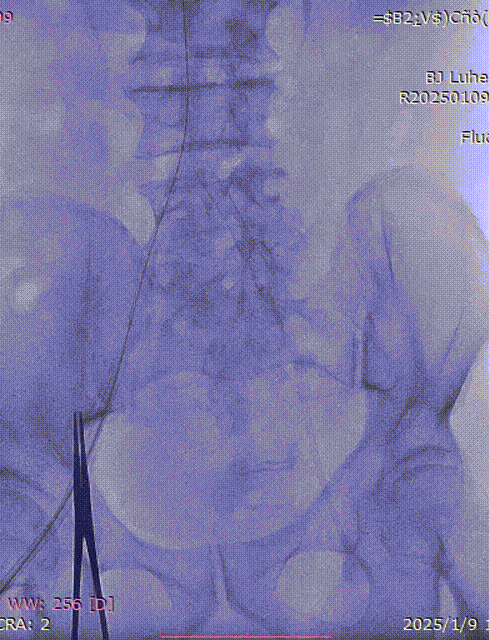

副入路球囊扩张

主入路球囊扩张

处理后下肢动脉造影